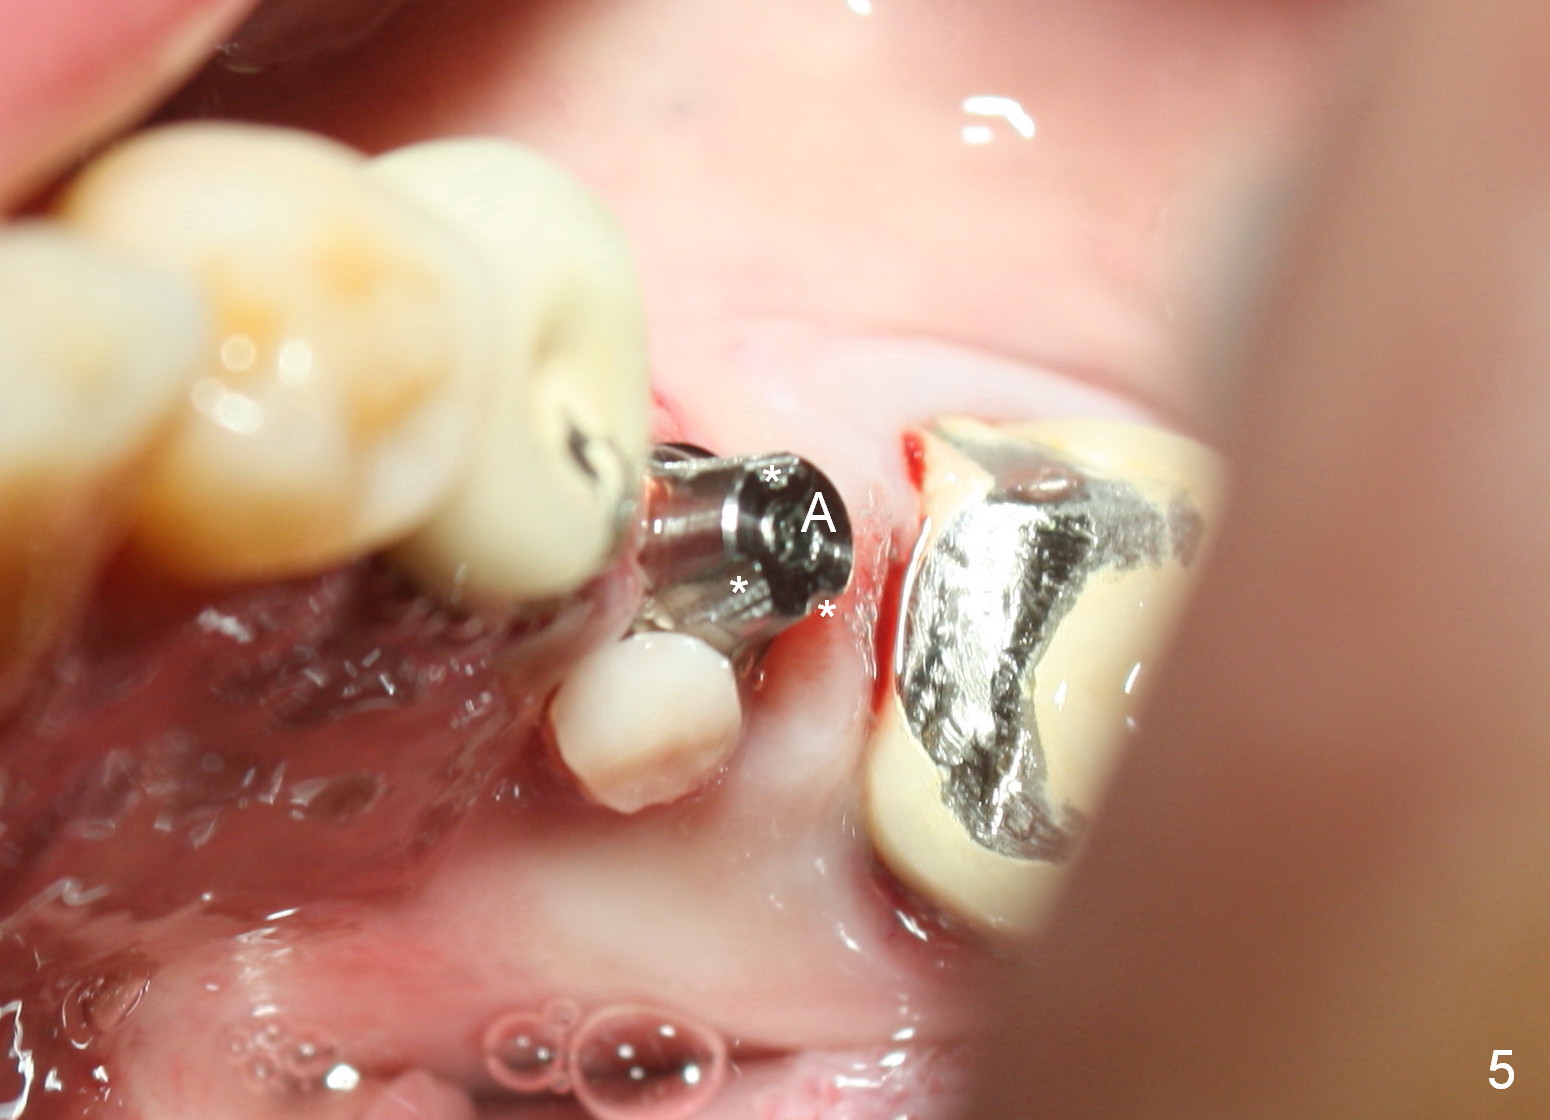

A 47-year-old man has history of bruxism, chipping porcelain from #29-31 FPD (Fig.1). Following sectioning the FPD, osteotomy is created (Fig.2: 5x14 mm drill) for placement of a 5x14 mm tissue-level implant (Fig.3,4). A 4x3 mm abutment (Fig.5 (lingual view) A) with 3 vertical slots (* for increased retention) is placed to retain periodontal dressing. The crown over the implant has dislodged 3 times over 28 months post cementation (Fig.6). It appears that the top of the abutment is too rounded. Clinical exam shows that the abutment height can be more, although the tooth #3 is supraerupted (Fig.7 (orthodontic intrusion is not indicated because of furca infection)).

Therefore a larger and longer abutment should be used (4.5x5 mm 0°). First of all, install Isolite. Remove cement from the access hole of the unipost with Cavitron. The cement was used to cement the crown. Use Tatum driver to remove the abutment. If it does not work, make a slot on the top of the abutment and use a regular screw driver to unscrew the abutment. Second, apply Cetacaine and perform laser gingivectomy to expose the implant margin. Temporary crown should be made to keep the margin and the space just created around the implant. Third try in the new abutment. Fourth reduce the abutment height carefully and make slopes corresponding the cusps of the opposing tooth. Reduce the opposing tooth if necessary. Last, consider Ketac cementation. Use resin bonding (with syringe tip) when an angled abutment is used. The bonding has higher retention than Ketac.